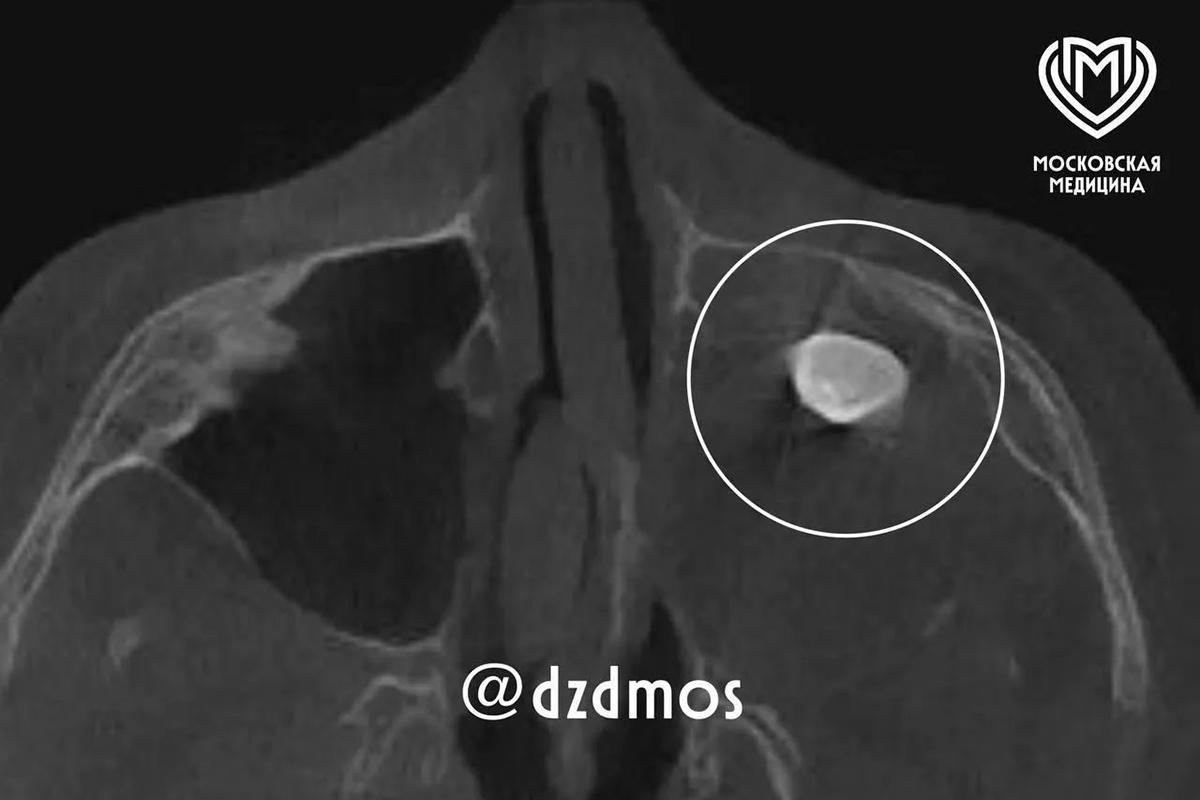

У 15-летнего москвича нашли зуб в носу.

Выросший в носу у 15-летнего москвича зуб нашли врачи Филатовской больницы. Специалистам удалось успешно удалить его, сообщает столичный депздрав в своем канале в Max.

Изначально подросток обратился к докторам из-за асимметрии лица и заложенности носа. Уточняется, что зуб у мальчика в гайморовой пазухе уже ранее нашли в частной клинике, однако родители хотели послушать стороннее мнение экспертов.

Сделав разрез, медики обнаружили новообразование — доброкачественную опухоль, в которой находился зуб. Операция прошла успешно, на данный момент пациента выписали, заложенность носа, мучившая его, исчезла. Также разрешились проблемы с асимметрией.